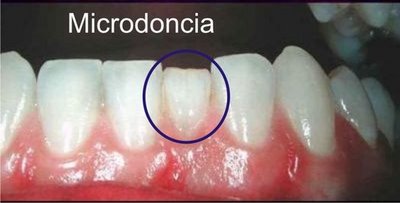

Microdoncia

Subtema

El tamaño dental se encuentra por debajo de los límites que se consideran normales.